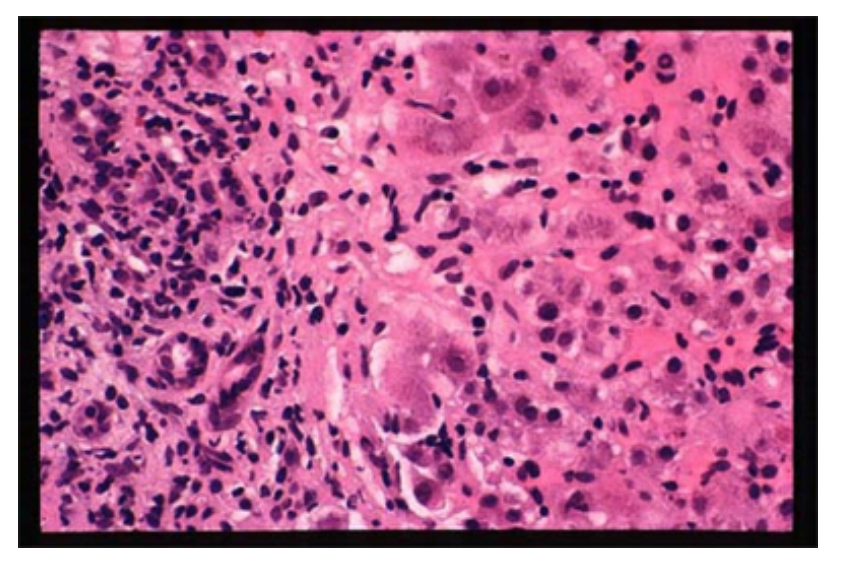

percutaneous liver biopsy (shown in pic)

what is the most likely diagnosis

autoimmune hepatitis

florid interface hepatitis (ie inflammation spilling over the portal tract limiting membrane on to the hepatocytes)

inflammatory exudate is rich in plasma cells

AIH most likely - female, elevated globulins, -ve viral serologies, no drug hx

bile ducts normal therefore primary biliary cholangitis unlikely